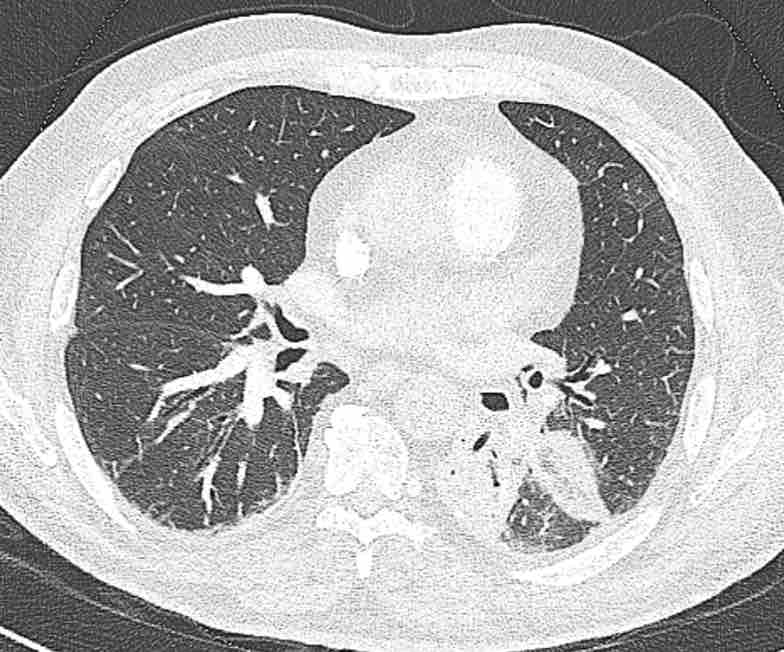

Cuộn qua các hình ảnh để quan sát khí quản phân chia thành phế quản chính phải và trái, sau đó tiếp tục phân chia thành các phế quản thùy và phế quản phân thùy.

Cuộn qua các hình ảnh để quan sát cách phổi được phân chia thành các phân thùy.